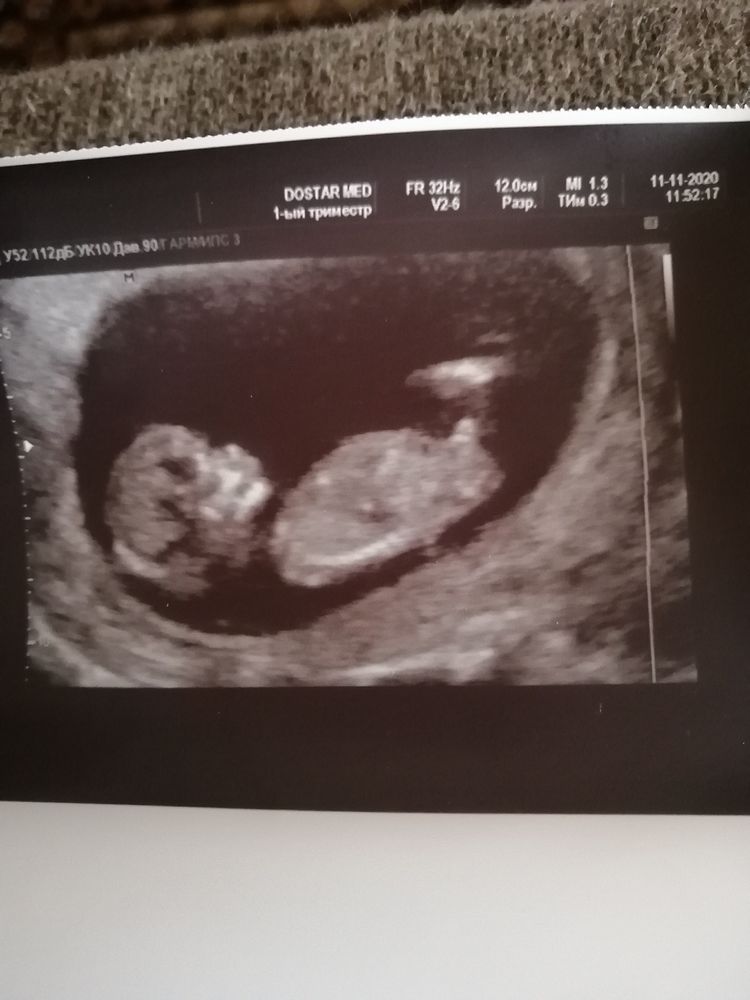

Опытные мамочки скажите кто у нас🤔

Тут без сомнения мальчишка💙💙💙

Красивый МАЛЬЧИШКА 💯 процентов 💙🙏🏻👣👣👣

Виктория, очень хотим мальчика после 3х девочек🙏

Мальчик 100%

Больше на мальчика похож )

Если это бугорок, то там мальчик) если это часть бедра, то не скажу)

Мама дочки и сыночка❤️❤️, врач на узи говорила что это бугорок

Значит парень)

На мальчика похож.

Как мальчик!? мальчик или девочка 16 нед ?